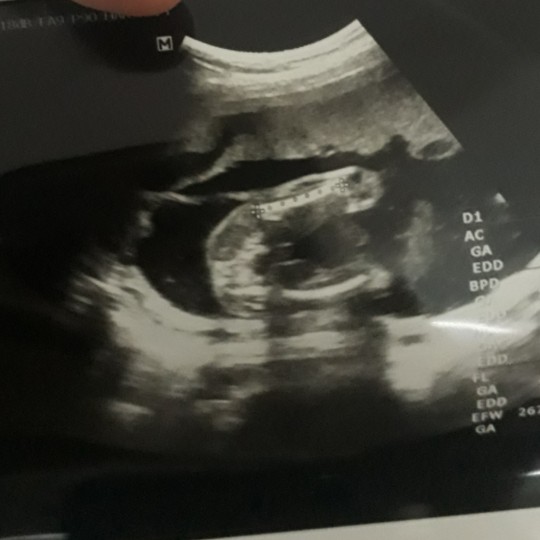

อยากเห็นอัตราซาวเพศลูกของแม่ๆ

อยากเห็นอัตราซาวเพศลูกของแม่ๆจังค่ะ อยากรุ้ว่า ผญ และผช ต่างกันยังไง